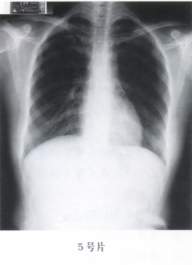

5.(5号片)

A、正常胸片

B、肺气肿

C、胸膜肥厚

D、气胸

E、肺炎

答案:1—6:EDACAC 15—20:ACBDED